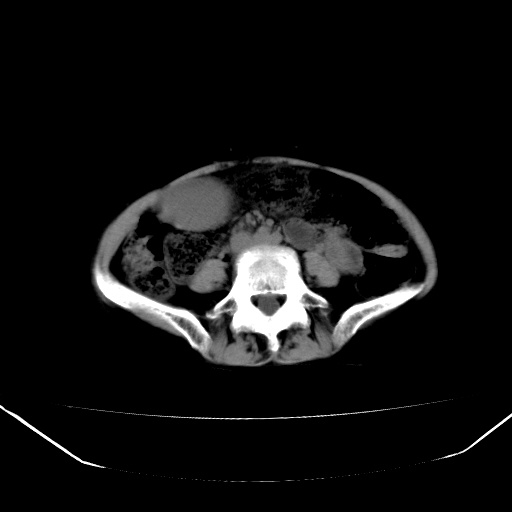

以下是引用jiangjing在2008-6-3 13:36:00的发言:[br]支持 胰头癌------肝内外胆管扩张,胰管扩张,胰头增大,增强见结节状轻度强化影,双管征明显

以下是引用卜一在2008-6-3 14:40:00的发言:[br]支持:胰头癌!(肝内外胆管扩张,胆囊高度扩张,胰管扩张,胰头增大,增强见结节状强化,明显低于胰腺强化密度,并明显见双管征)

以下是引用dyqct在2008-6-3 14:54:00的发言:[br]支持 胰头癌伴肝内外胆管扩张,胰管扩张,胰头增大,增强见结节状轻度强化影,双管征明显。肠系膜上静脉已受侵(已不能手术),建议离子植入治疗吧。